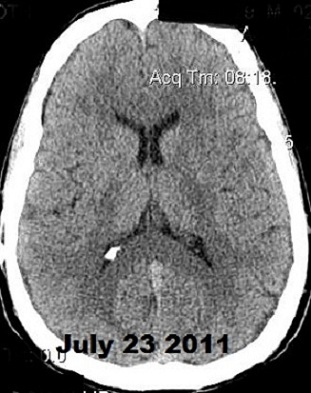

Below, are my CT images beginning on Jan. 17, 2011, where there is enlargement of the ventricles, followed by further enlargement on April 9, 2011, and what appears to be more enlargement on June 8, 2011, despite my May 23, 2011 revision. Then, there appears to be a slight decrease in ventricular enlargement on June 20, 2011, followed by normal size (almost too small) ventricles on July 23, 2011. We felt my ventricles came down in size too quickly, and began to raise the proGav setting over a period of two months, eventually up to 6, and rescanned me on Sept. 15, 2011. Those results indicated my ventricular enlargement had returned, so the proGav was returned to a lower setting of 2.

Under my CT images below, I list each of the proGAV's corresponding settings. It was initially set at 10 during surgery, with no improvement in complaints after one week, I asked that it be lowered to 7, and one week later to 5, then to 3, and finally to 0. During this period, almost every morning I awoke with a substantial headache that I assumed was due to increased ICP and underdrainage. On the June 20, 2011, CT we could finally see some decrease in the dilation of my ventricles, and determined the shunt to be working. But, we were still puzzled by the ongoing awaking a.m. headaches. For this reason, it was temporarily raised to a setting of 2, and then with no relief back down to 0. It remained at 0 for almost a month when the July 23, 2011 scan revealed normal sized ventricles.  Because of the relatively short period it took for my ventricles to come back to normal, we raised the proGAV gradually to 6, and back down to 2 after the Sept. 15, 2011 scan showed a return of ventriculomegaly.

June 8, 2011 proGAV  5/20    June 20, 2011 proGAV 3/20      July 23, 2011 proGAV 0/20    Sept. 15, 2011 proGav 6/20   Feb. 1, 2012 proGav 0/20